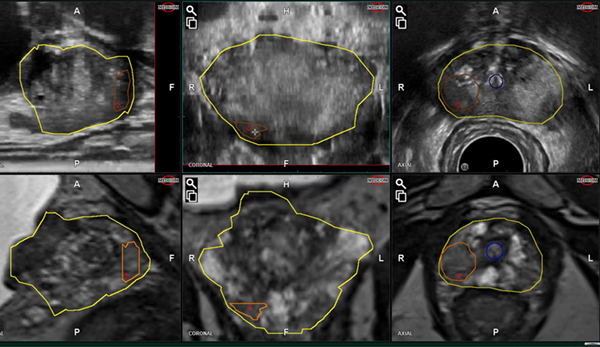

MRI-USフュージョン前立腺生検をサポートした泌尿器科向けOne-Cartソリューション

検査前に,標的部位と系統的生検のための生検部位の事前プランニングを行います。カスタマイズされた前立腺の解剖学的モデルを適用することで,系統的生検のルーチンの手順を容易にすることができます。

プランニングされた生検位置が3Dデータ上に表示されるため,前立腺内の生検範囲をより正確に評価することができます。生検前に高精度に針の軌道を確認することで,的確なターゲティングを行うことができます。

フュージョンと動きの補正

剛性 (Rigid) フュージョンに加えて,弾性 (Elastic) フュージョンにも対応しています。また,前立腺の動きをリアルタイムに追従し,体動等による位置のずれを補正して表示することで,安全なフュージョン生検をサポートします。